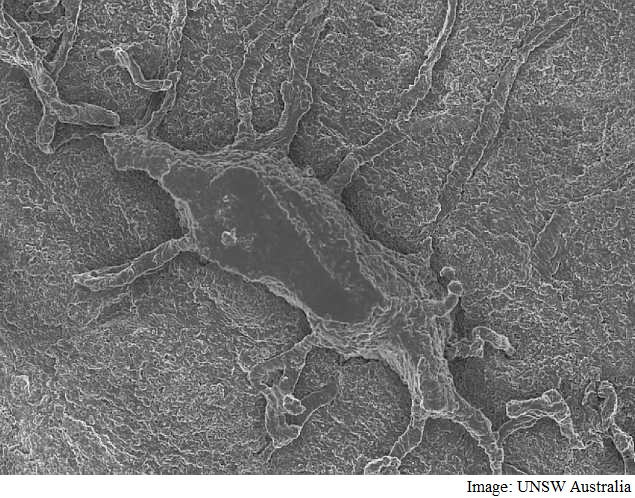

IIT-Mandi Startup Develops AI-Based Medical Imaging Solution to Detect Respiratory, Genetic Disorders

- Monday May 1, 2023

The innovators at Dectrocel Healthcare have developed a platform in which digital and analogue chest X-Ray images and pictures of children are uploaded and, in a few minutes, the algorithm is able to diagnose respiratory abnormalities that have significant mortalities such as tuberculosis and Chronic Obstructive Pulmonary Disease (COPD).